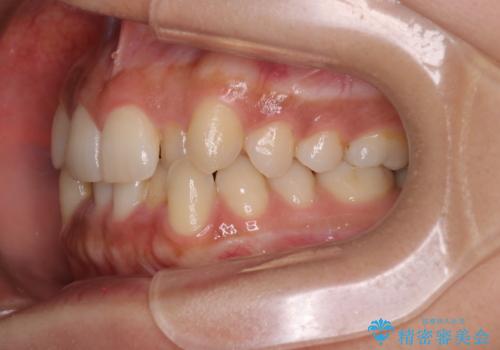

反対咬合と前歯のガタガタを非抜歯で改善

- 患者様は、上下の前歯のガタガタと反対咬合(下の歯が上の歯より前に出ている状態)を主訴として来院されました。診断の結果、抜歯を行わずに治療を進めるため、臼歯を遠心移動させてスペースを作り、IPR(インタープロキシマルリダクション)で歯間を調整する治療計画を立てました。インビザラインを使用して、透明で目立たない矯正装置により、歯列を整えながら噛み合わせも改善することを目標としました。

非抜歯での治療では、限られたスペースの中で効率的に歯を動かす必要があります。本症例では、臼歯を後方に移動させる遠心移動を行い、歯列のガタガタを改善しました。また、IPRを適切に行うことでスペースを確保し、歯根や歯肉への負担を最小限に抑えながら治療を進めました。インビザラインを使用することで、治療中も目立ちにくく、患者様の日常生活への影響を軽減しました。結果として、抜歯を行わずに美しい歯並びと自然な噛み合わせを実現し、患者様には大変満足していただけました。